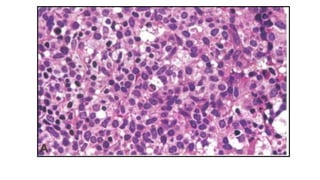

BLASTIC PLASMACYTOID DENDRITIC CELL

NEOPLASM

• Clinically aggressive neoplasm derived from the precursors of

plasmacytoid dendritic cell

• Mean age 61-67 years

• M:F ratio is 3.3:1

• Mostly involves skin(64-100%) followed by bone marrow,

peripheral blood (60-90%) & lymph node (40-50%)

CLINICAL FEATURES

• Skin manifestations - most frequent

• The diagnosis is made on skin biopsy

• Three types of lesions

 isolated (one or few) purplish nodule type (two thirds of cases)

: head & lower limbs

 isolated (one or few) bruise-like papule type

 disseminated type with purplish nodules and/or papules

and/or macules : most characteristic

• In some patients lacking skin involvement and with leukaemic

presentation, the diagnosis is made based on peripheral blood

or bone marrow analyses

• In most cases, a fulminant leukaemic phase ultimately develops

• About 10-20% cases associated with or develop into other

myeloid disorders, most commonly CMML, MDS or AML